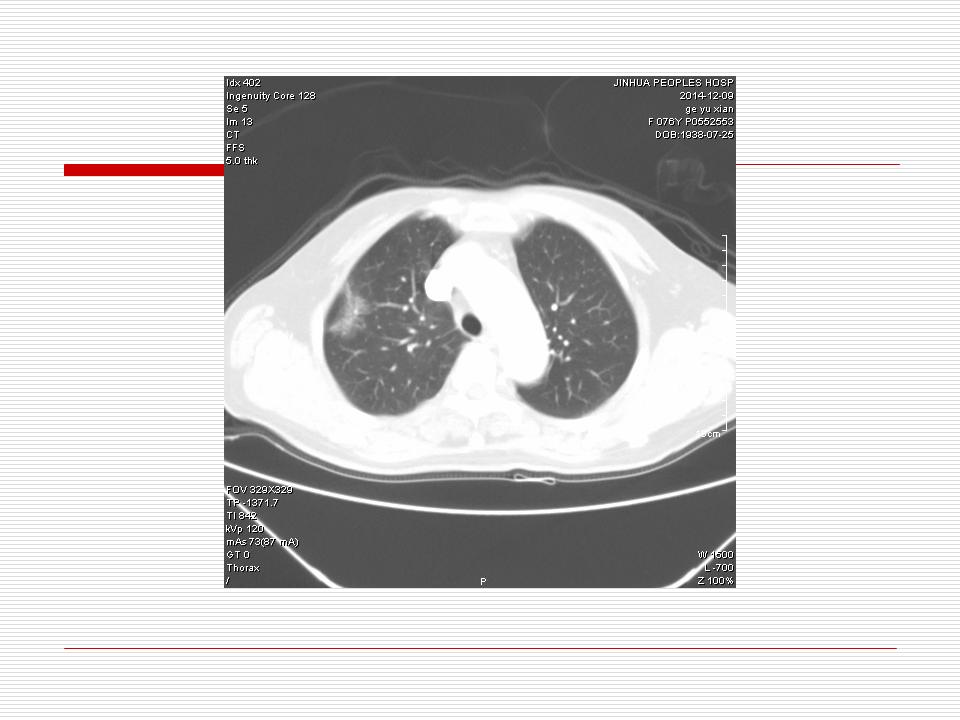

肺部阴影永恒且最重需要鉴别的是:到底是炎症还是肿瘤?但临床的病例中的影像表现难以界定或有些肿瘤特征,同时又有些炎症特点是非常常见的情况。作为临床医生我们怎么去总结分析,并找到之所以是炎症或之所以是肿瘤的细微差别或特点非常重要,也非常有用。2019.12.7浙江省2019年胸心外科学学术年会在宁波召开时,我的临床病例分析与经验总结<那些像肺癌的炎症与像炎症的肺癌>获得在大会交流的机会,以下为该PPT的内容,与你分享,希望对同道有益,有借鉴与启迪。若有探讨与进一不完善的建议,欢迎文末留言讨论: